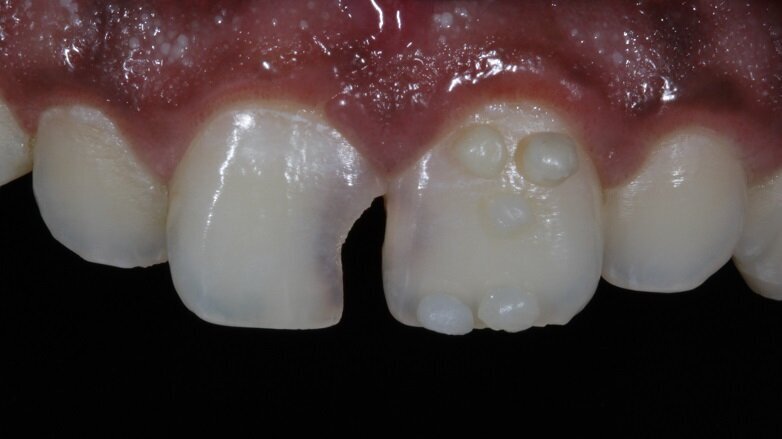

A 21 year old male reported to the clinic with a chief complaint that he was unhappy with his smile as he had a gap in between his front two teeth. He wanted a quick fix and had high aesthetic demands. Pre-operative photographs were taken at this point (Fig 1). On examination, tooth 11 showed decay mesially all the way extending upto the incisal edge (Class IV cavity). Tooth 21 also showed mesial decay only from the palatal aspect (Class III cavity).

Vitality test was performed and the result was positive, thus no endodontic treatment was required. Pre-operative analysis showed that due to a longstanding decay on 11 , 21 tipped mesially. This resulted in a slight shift in midline (Fig 2). On measuring the mesio-distal width of both the central incisors, they showed a discrepancy (Fig 2).

Fig 1: Pre-operative photograph

Fig 2: mesial tipping of 21

Discrepancy in mesio-distal width